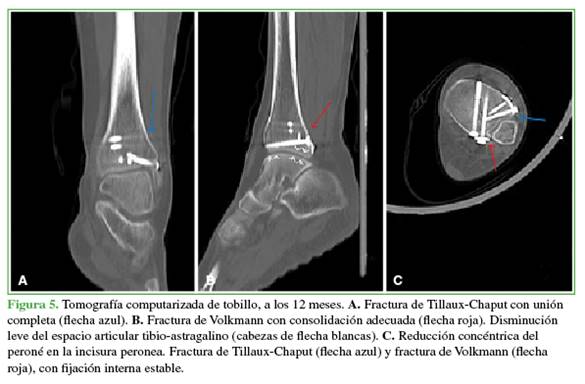

Después de 12 meses, se documentó la consolidación de las fracturas (Figuras 4 y 5), y la paciente reanudó sus actividades habituales; el puntaje de la American Orthopaedic Foot and Ankle Society era de 91 y el de la escala funcional de Olerud-Molander de 95 (Figura 6).